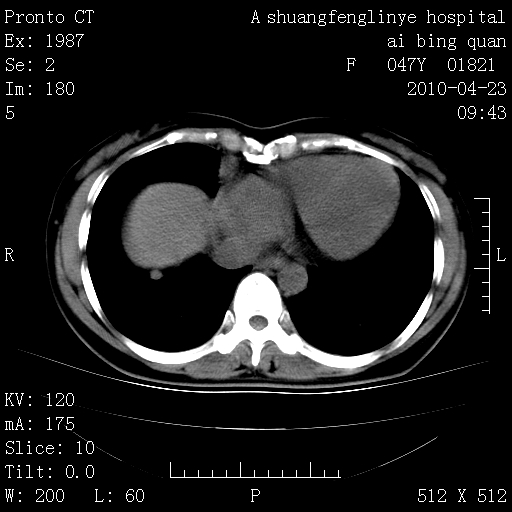

标题: CT25944:胸痛、气短、前几日高烧!肺Ca?请会诊! [打印本页]

标题: CT25944:胸痛、气短、前几日高烧!肺Ca?请会诊!

双肺多发结节,考虑转移瘤,肺癌肺转移不除外

双肺多发结节,部分密度较高,最大结节边缘光滑。临床有“胸痛、气短、前几日高烧”病史。首选考虑:右肺感染性病变!建议积极消炎后复查!